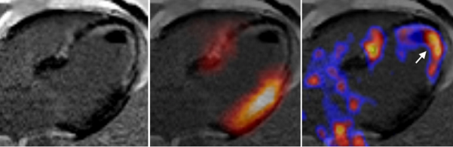

April 2021: Imaging of cardiac fibroblast activation in a patient after acute myocardial infarction using 68Ga-FAPI-04.

Notohamiprodjo S, Nekolla SG, Robu S, Villagran Asiares A, Kupatt C, Ibrahim T, Laugwitz KL, Makowski MR, Schwaiger M, Weber WA, Varasteh Z.

J Nucl Cardiol. 2021 Apr 15. doi: 10.1007/s12350-021-02603-z